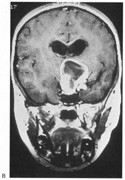

Fig. 18. Magnetic resonance imaging scan of patient with stroke causing a right hemiachromatopsia as well as partial superior quadrantanopia.

Achromatopsia in the contralateral hemifield alone can follow unilateral right or left occipital lesions (Fig. 18). Patients are typically asymptomatic until the defect is demonstrated on examination.234,235 Hemiachromatopsia is usually associated with a superior quadrantanopia;234,235,241 therefore, the color defect is only demonstrable in the remaining inferior quadrant. The preserved color vision in the ipsilateral hemifield allows normal or near-normal performance on centrally viewed tests of color vision such as pseudoisochromatic plates. The incidence of hemiachromatopsia is probably underestimated, given its asymptomatic nature and the failure of routine clinical color tests to detect its presence.

HEMIACHROMATOPSIA.